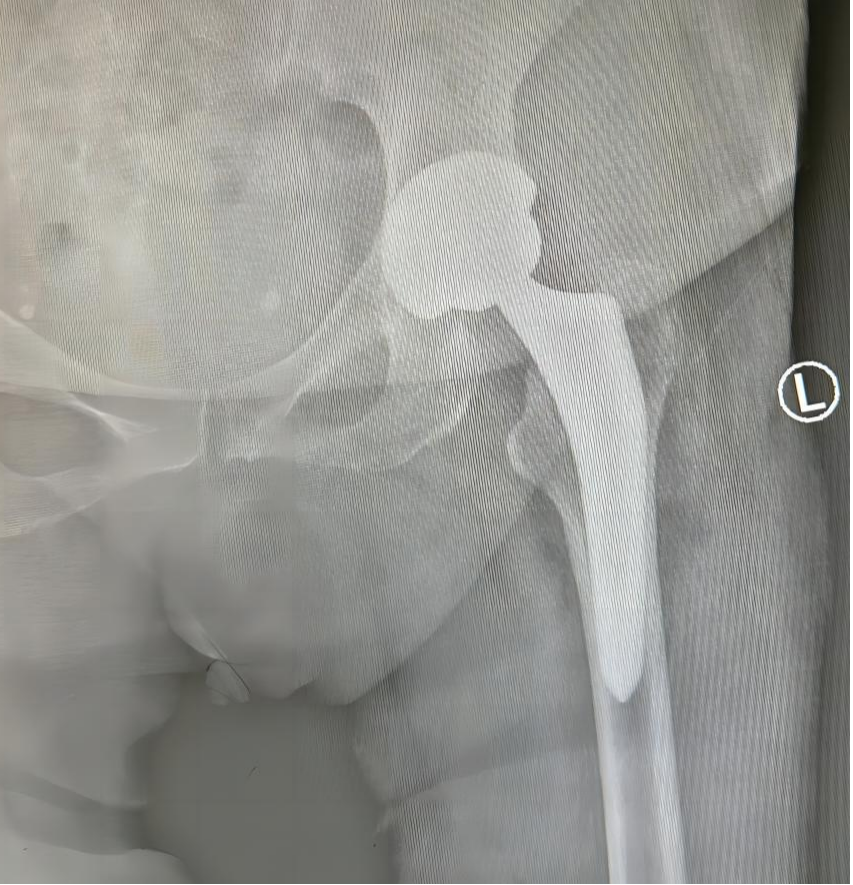

三、多功能牵引床辅助下直接前路(DAA)人工全髋关节置换术以及椭圆形髋臼假体、多翼型髋臼假体和双动型髋关节假体。牵引床的应用,更多地解放了医生的双手,在节省人力的同时,还为手术提供了稳定而持久的牵引力,极大地降低了髋关节置换的手术难度,使手术进行更加顺利。椭圆形髋臼、多翼型髋臼和双动型髋关节的问世,增加了髋关节的稳定性,为复杂的髋关节病例提供了有效的解决方案。